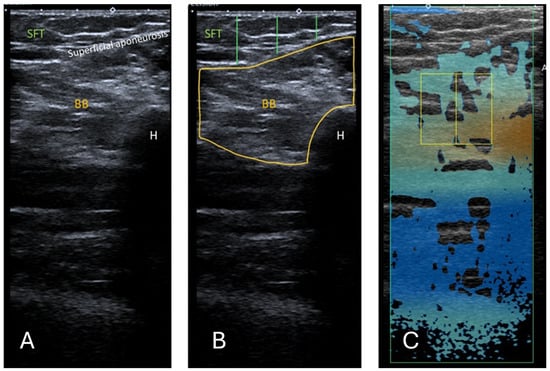

10 US images were obtained for RF and 5 for BB (15 images per participant total), as shown in Figure 1 and Figure 2. The images were anonymised and saved as DICOM files for EI measurements.

Figure 2. (A) Ultrasound B-mode image of the BB. The distance between the epidermis and superficial aponeurosis is defined as SFT. (B) Segmented image of the BB, including the muscle cross-sectional area and the lines marking the thickness of the SFT from the lateral, central, and medial aspects of the BB. The measurement of the SFT was taken at 25%, 50%, and 75% of the length of the total muscle visible on ultrasound, respectively. (C) Attenuation imaging of the BB. The green box indicates the area of interest (AOI), and the yellow box indicates the region of interest (ROI) placed within the BB. BB = biceps brachii, SFT = subcutaneous fat tissue, H = humerus.

2.2.1. Echo Intensity

The images were processed using a computer-assisted greyscale analysis using ImageJ software (version 1.54h) [34]. Echo intensity is defined as the mean pixel intensity within the region of interest (ROI) and was calculated using the histogram function. The mean voxel intensity is expressed as a value ranging between black (0 arbitrary units) and white (255 arbitrary units). The RF and BB muscle cross-sections were circled manually to include as much of the muscle as possible, excluding any bone or surrounding myofascial tissue, as shown in Figure 1B and Figure 2B. A total of 5 consecutive images per level were taken, and the muscle was circled manually. The average of the 5 measurements was used in the analysis. When it was insufficient to display the entire muscle, only a part of the muscle was used for EI analysis. EI is taken only from transverse images for a fair and accurate comparison with ATI. The thickness of the subcutaneous fat tissue (SFT) was defined as the length from the epidermis to the superficial aponeurosis. For each transverse image, the SFT was drawn at 25%, 50%, and 75% of the total length of the BB or RF muscle visible on the ultrasound image, as shown in Figure 1B and Figure 2B. The average of these 3 lines was taken to have the distance for SFT. The average of the 5 measurements for SFT was used in the final analysis.

2.2.3. Attenuation Imaging

The commercially available Canon linear array i11LX3 (Canon, Otawara-shi, Japan) with a centre frequency of 7 MHz was used to complete ATI of the RF and BB muscles. Attenuation imaging general (ATI-Gen) was the pre-set of the Aplio i800. The machine settings, such as a gain of 76 dB and dynamic range of 60, were kept consistent between participants. The depth of the image field was 10 cm when the area of interest (AOI) box was at maximum and as near to the middle of the frame as feasible, as shown in Figure 1C for RF and Figure 2C for BB. The ROI box was made to cover as small an area as possible (2 × 2 cm) and moved on the image so that R2 was greater than 0.85. Previous studies used an R2 value of 0.7 [24]; hence, 0.85 was deemed acceptable here. The box was positioned on the thigh to contain only the RF, where possible. This was not always possible due to the limitations in the smallest area of ROI available. In this case, the box was positioned on the RF, vastus intermedius, and medius muscles, including myofascial tissue. As the transverse cross-section of BB muscle is larger, the box can be positioned here so that no bone or muscle fascia lies on it as far as possible. Examples of the ATI measurement are shown in Figure 1 and Figure 2.